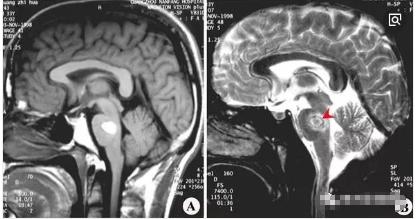

四、桥脑出血:

桥脑是脑干出血的好发部位。早期表现病处侧面瘫,对侧肢体摊,称为交叉性瘫。这是桥脑出血的临床特点。如果出血量大,则影响对侧,出现四肢瘫、瞳孔缩小、高热、昏迷等症;如果血液破入第四脑室则出现抽搐、呼吸不规则等严重症状,预后多不好。

桥脑可见短T1混杂t2信号,边界清晰,有轻度占位效应。